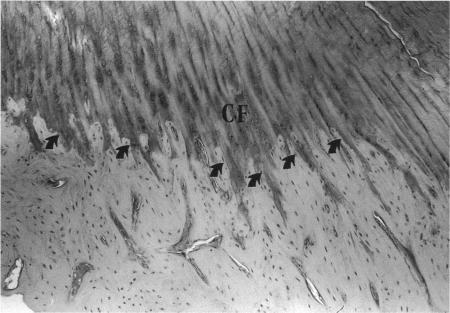

At chondral ligament insertions the calcified fibrocartilage interdigitates deeply with the lamellar bone. The shape of this interface is formed under physiological loading conditions. For the purpose of morphological comparison between different ligament entheses in the rabbit knee, the number and frequency of interdigitations and thickness of calcified fibrocartilage were quantitated at the femoral insertion of the medial collateral ligament, both insertions of the cruciate ligaments, and the tibial insertion of the patellar ligament. Among the insertions, the femoral insertion of the medial collateral ligament showed the lowest frequency and depth of interdigitations at the soft tissue-bone interface, but had the thickest zone of calcified fibrocartilage. An inverse relationship was found at the insertion interface of the cruciate and patellar ligaments. The frequency and depth of interdigations at the bone-soft tissue interface at different chondral entheses seem to be related to the mechanical strength of the respective ligament; meanwhile it may be hypothesised that the thickness of the calcified fibrocartilage might be more related to the amount of motion which takes place at an insertion.

在软骨韧带附着处,钙化纤维软骨与板层骨深度交错。该界面的形状是在生理负荷条件下形成的。为了对兔膝关节不同韧带附着点进行形态学比较,对内侧副韧带股骨附着点、交叉韧带的两个附着点以及髌韧带胫骨附着点的交错数量和频率以及钙化纤维软骨的厚度进行了定量分析。在这些附着点中,内侧副韧带股骨附着点在软组织 - 骨界面处的交错频率和深度最低,但钙化纤维软骨带最厚。在交叉韧带和髌韧带的附着界面发现了相反的关系。不同软骨附着点处骨 - 软组织界面的交错频率和深度似乎与相应韧带的机械强度有关;同时可以推测,钙化纤维软骨的厚度可能与附着点处发生的运动量更相关。